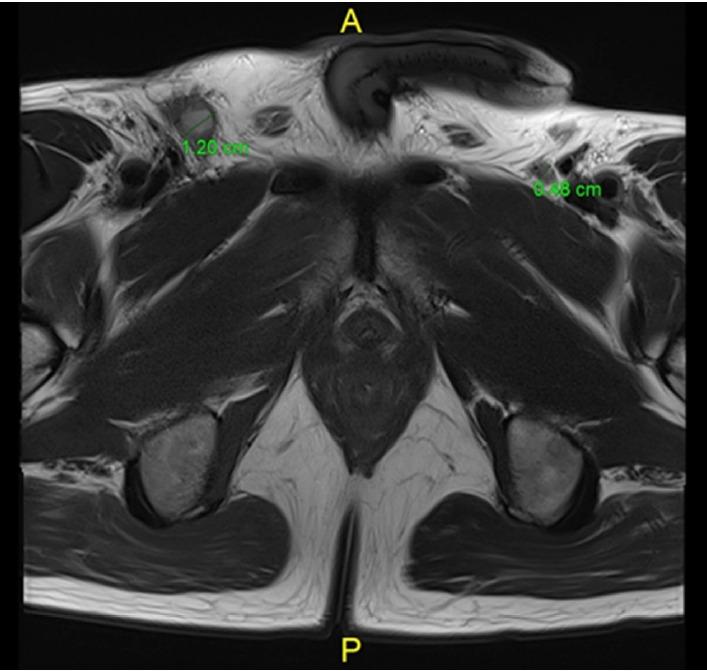

Despite innovative advancements, distally located rectal cancer remains a critical disease of challenging management. The crucial location of the tumor predisposes it to a circumferential resection margin (CRM) that tends to involve the anal sphincter complex and surrounding organs, with a high incidence of delayed anastomotic complications and the risk of the pelvic sidewall or rarely inguinal lymph node metastases. In this regard, colorectal surgeons should be aware of other issues beyond total mesorectal excision (TME) performance. For decades, the concept of extralevator abdominoperineal resection to avoid compromised CRM has been introduced. However, the complexity of deep pelvic dissection with poor visualization in low-lying rectal cancer has led to transanal TME. In contrast, neoadjuvant chemoradiotherapy (NCRT) has allowed for the execution of more sphincter-saving procedures without oncologic compromise. Significant tumor regression after NCRT and complete pathologic response also permit applying the watch-and-wait protocol in some cases, now with more solid evidence. This review article will introduce the current surgical treatment options, their indication and technical details, and recent oncologic and functional outcomes. Lastly, the novel characteristics of distal rectal cancer, such as pelvic sidewall and inguinal lymph node metastases, will be discussed along with its tailored and individualized treatment approach.

尽管有创新性进展,但低位直肠癌仍然是一种管理具有挑战性的关键疾病。肿瘤的关键位置使其易出现环周切缘(CRM)累及肛门括约肌复合体和周围器官的情况,吻合口延迟并发症的发生率很高,且存在盆腔侧壁或极少出现的腹股沟淋巴结转移风险。在这方面,结直肠外科医生应意识到全直肠系膜切除(TME)操作之外的其他问题。几十年来,为避免CRM受损而引入了经肛提肌腹会阴联合切除术的概念。然而,低位直肠癌深部盆腔解剖的复杂性以及视野不佳导致了经肛全直肠系膜切除术的出现。相比之下,新辅助放化疗(NCRT)使得在不影响肿瘤学疗效的情况下能够实施更多保留括约肌的手术。NCRT后显著的肿瘤退缩和完全病理缓解在某些情况下也允许采用观察等待方案,现在有了更确凿的证据。这篇综述文章将介绍当前的手术治疗选择、其适应证和技术细节,以及近期的肿瘤学和功能结局。最后,将讨论低位直肠癌的新特征,如盆腔侧壁和腹股沟淋巴结转移,以及其针对性的个体化治疗方法。